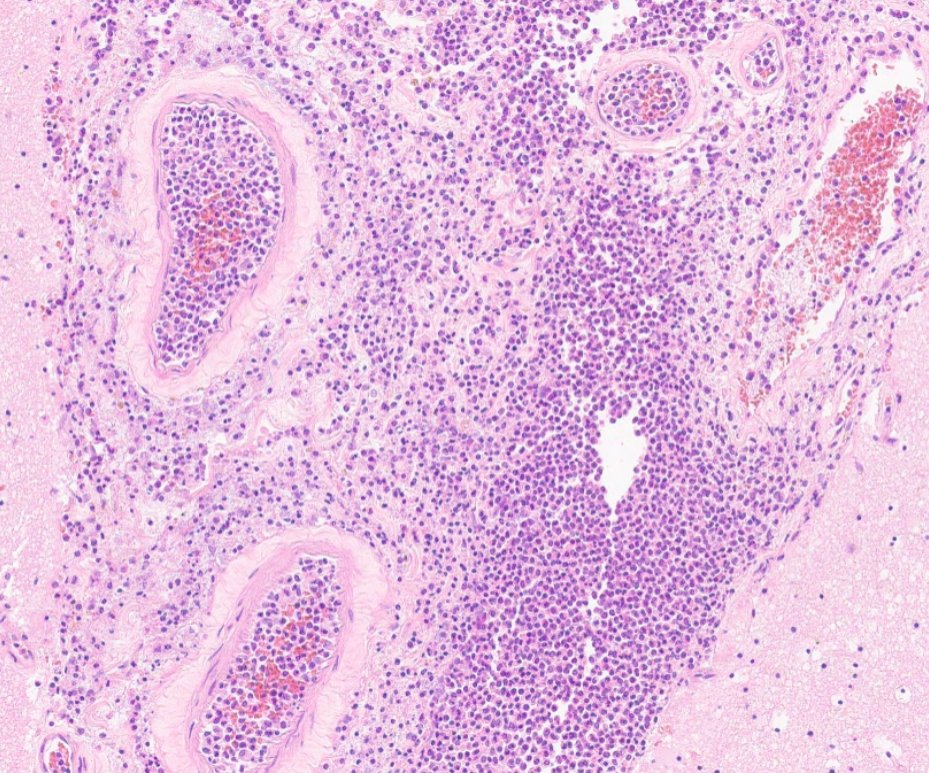

Since 2003, we have been creating one of the largest pathology educational resources online.. completely open access and free to use for non-commercial activities.. please get in touch for educational collaboration or commercial use 👍 any use pls credit: virtualpathology.leeds.ac.uk